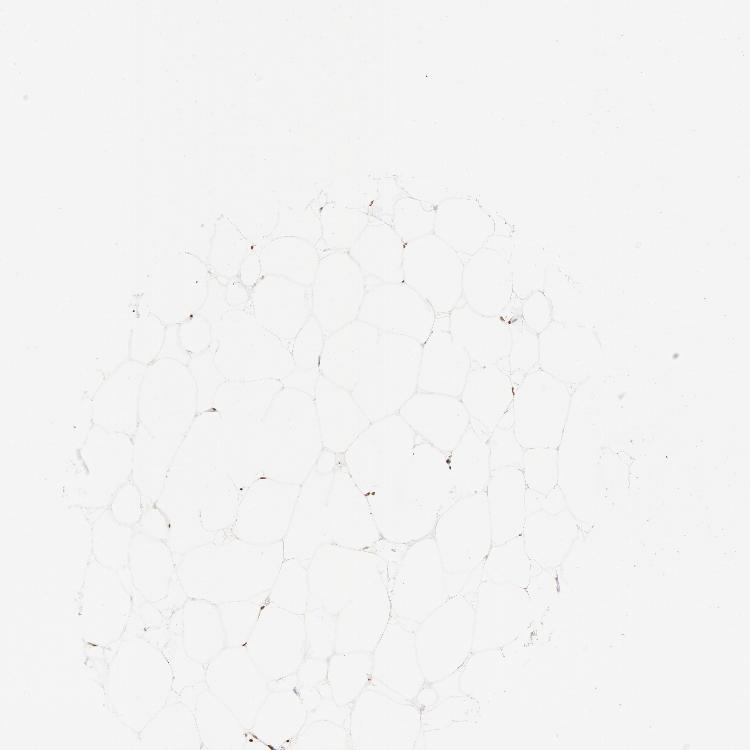

SOFT TISSUE 1 - Antibody stainingi

Antibody staining in the annotated cell types in the current human tissue is reported as not detected, low, medium, or high, based on conventional immunohistochemistry profiling in selected tissues. This score is based on the combination of the staining intensity and fraction of stained cells.

Each image is clickable and will lead to virtual microscopy that enables deeper exploration of all samples and also displays staining intensity scores, fraction scores and subcellular localization as well as patient and tissue information for each sample.

SOFT TISSUE 2 - Antibody stainingi